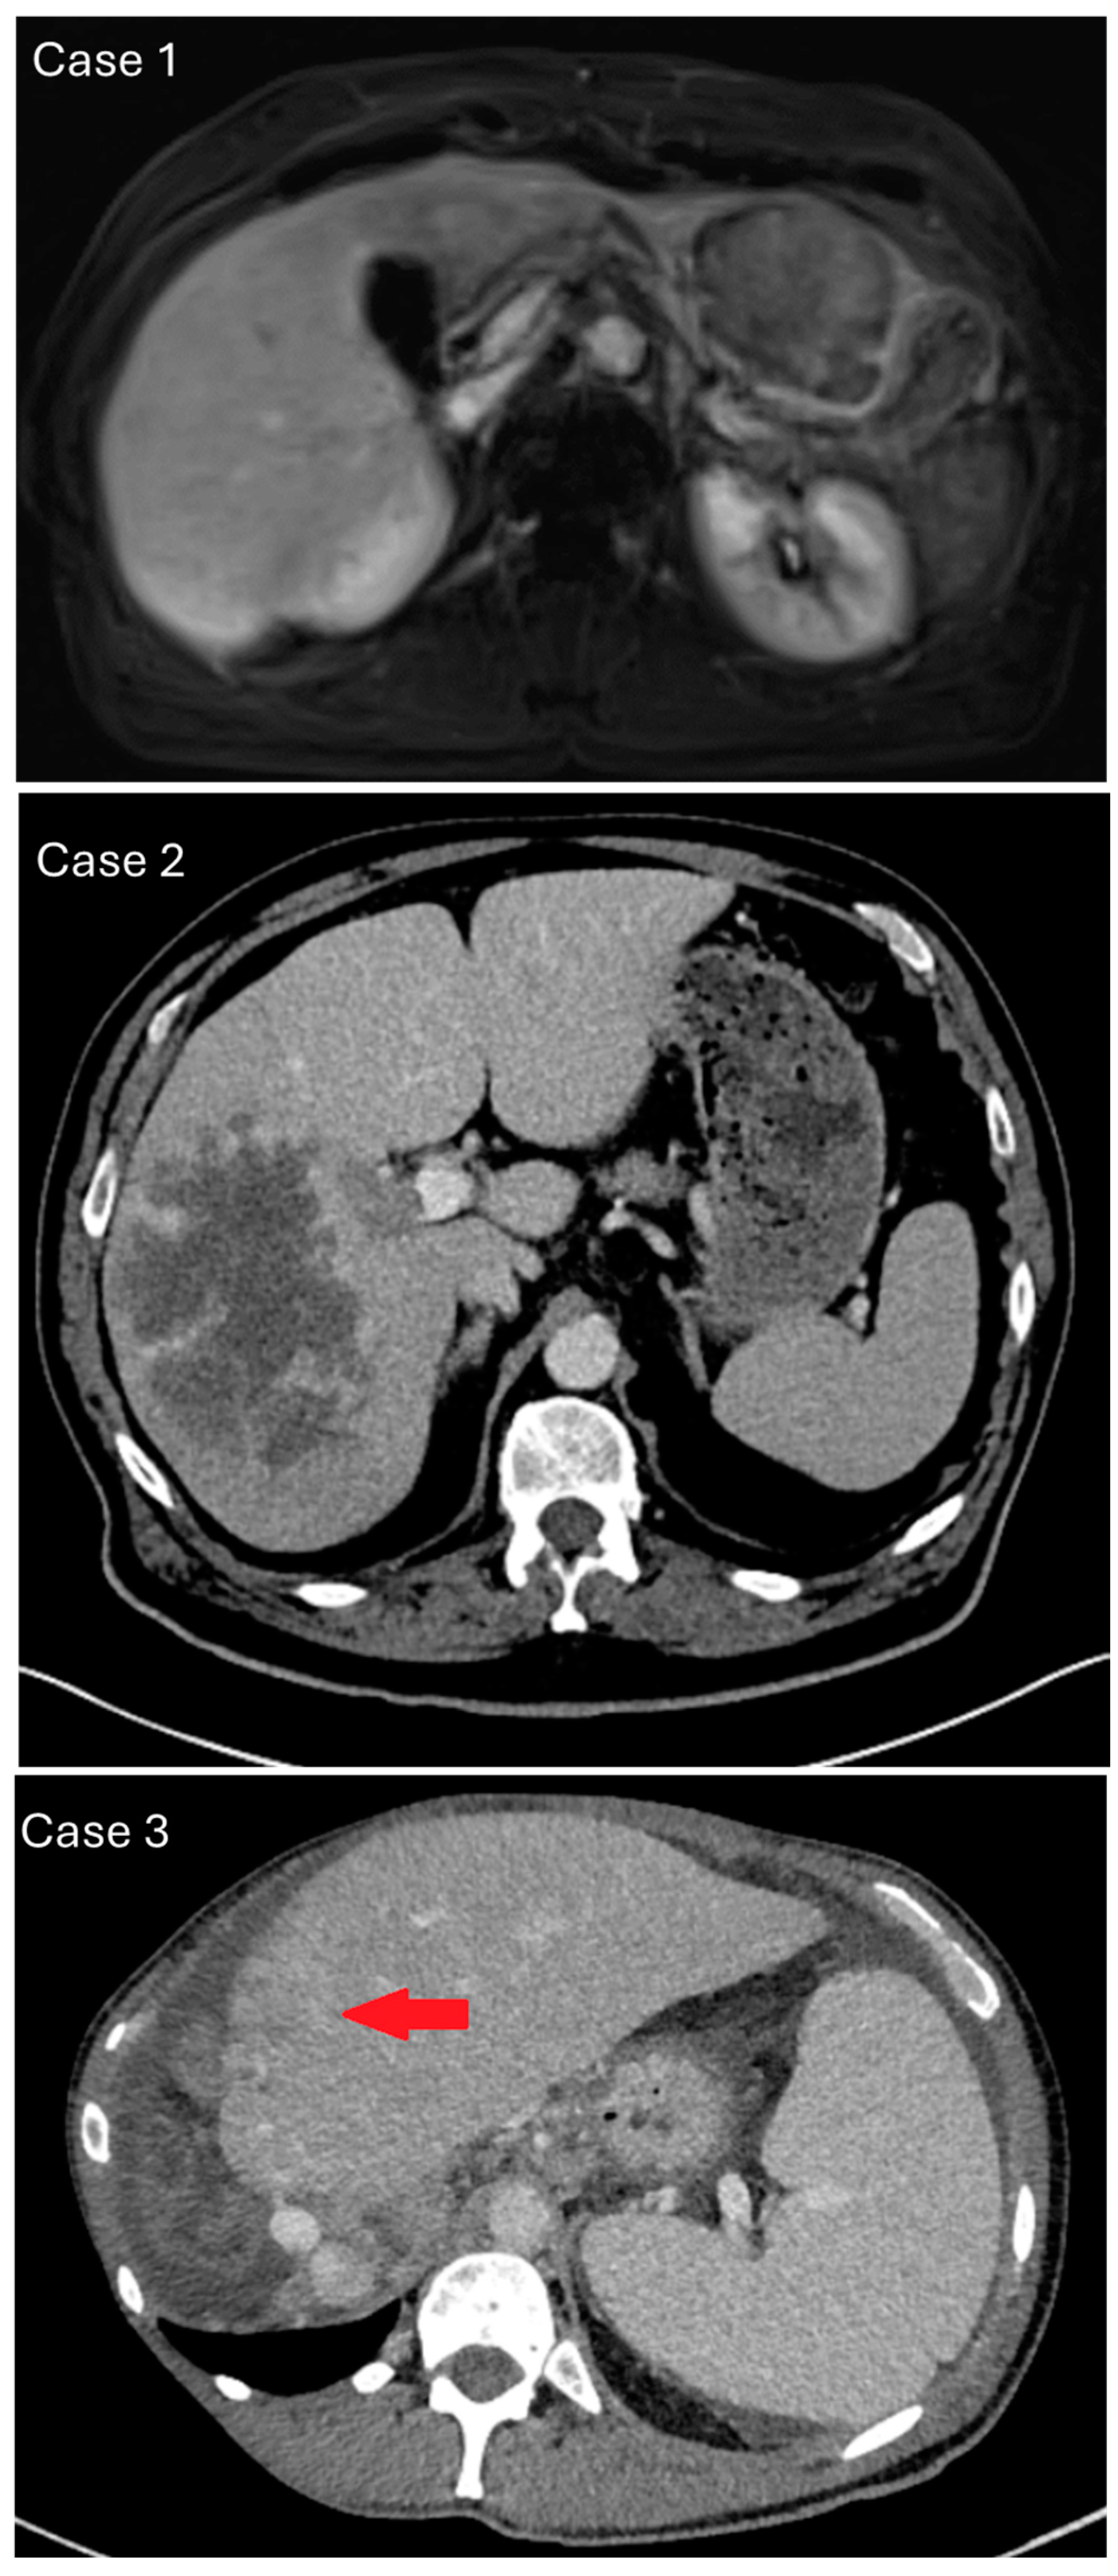

2. Materials and Methods

3. Results